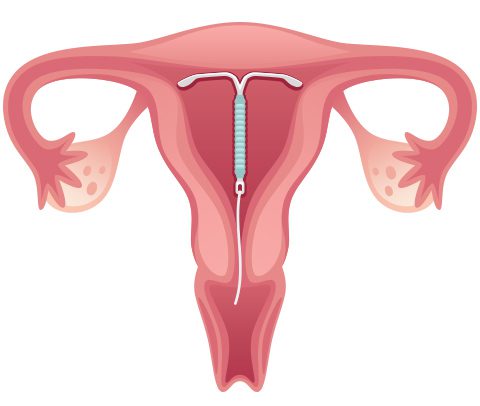

تطبيقات اللولب الرحمي “IUD” هو أحد تطبيقات الجهاز الطبي داخل الرحم للمساعدة في منع الحمل، وهو من أولويات بعض العائلات التي ترغب في تنظيم عدد الافراد. قد يكون هذا لأسباب اقتصادية بسبب نقص الدخل، أو لأسباب مرضية أن هناك خطر على الأم في المواقف التالية الحمل أو أسباب اجتماعية أخرى.

اللولب هو جهاز على شكل حرف T مصنوع من مواد مختلفة. مثل: البلاستيك والنحاس والبلاتين، تختلف المدة الفعالة لللفات لمنع الحمل باختلاف جودتها. هذا يختلف من ثلاث سنوات إلى عشر سنوات.

خطوات تركيب اللولب

- الخطوة الأولى

- يقوم طبيب أمراض النساء بفحص المهبل والرحم؛ وبعد التأكد من خلو السيدة من أية التهابات تمنع تركيب اللولب يبدأ في تعقيم وتطهير الرحم، والهدف من ذلك منع انتشار البكتيريا أو الفطريات خلال عملية التركيب.

- الخطوة الثانية

- يقوم الطبيب بإدخال قطعة معدنية برفق؛ من أجل وصول اللولب إلى عنق الرحم بسهولة، ويقوم بقياس طول عمق الرحم، ويجب أن يكون بين 6-9 سم، وفي حالة كون الرحم أقل من ذلك من حيث العمق، فيجب استخدام وسيلة أخرى.

- الخطوة الثالثة

- هذه هي الخطوة الأخيرة في عملية تركيب اللولب، حيث يقوم الطبيب بوضع اللولب أمام الأنبوب، ويقوم بإدخاله وتثبيته، ثم يسحب الأنبوب برفق، ثم يقطع جزءًا من خيط اللولب، فلا داعي للقلق بشأن جزء من اللولب. سلك طوله أقل من 2 سم ويظهر في الرقبة خارج الرحم أو فتحة المهبل، حيث يساعد ذلك على إزالة اللولب إذا لزم الأمر في المستقبل.